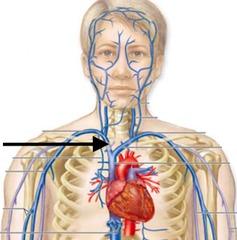

Brachiocephalic vein

Subclavian artery/vein

Superior/inferior vena cava